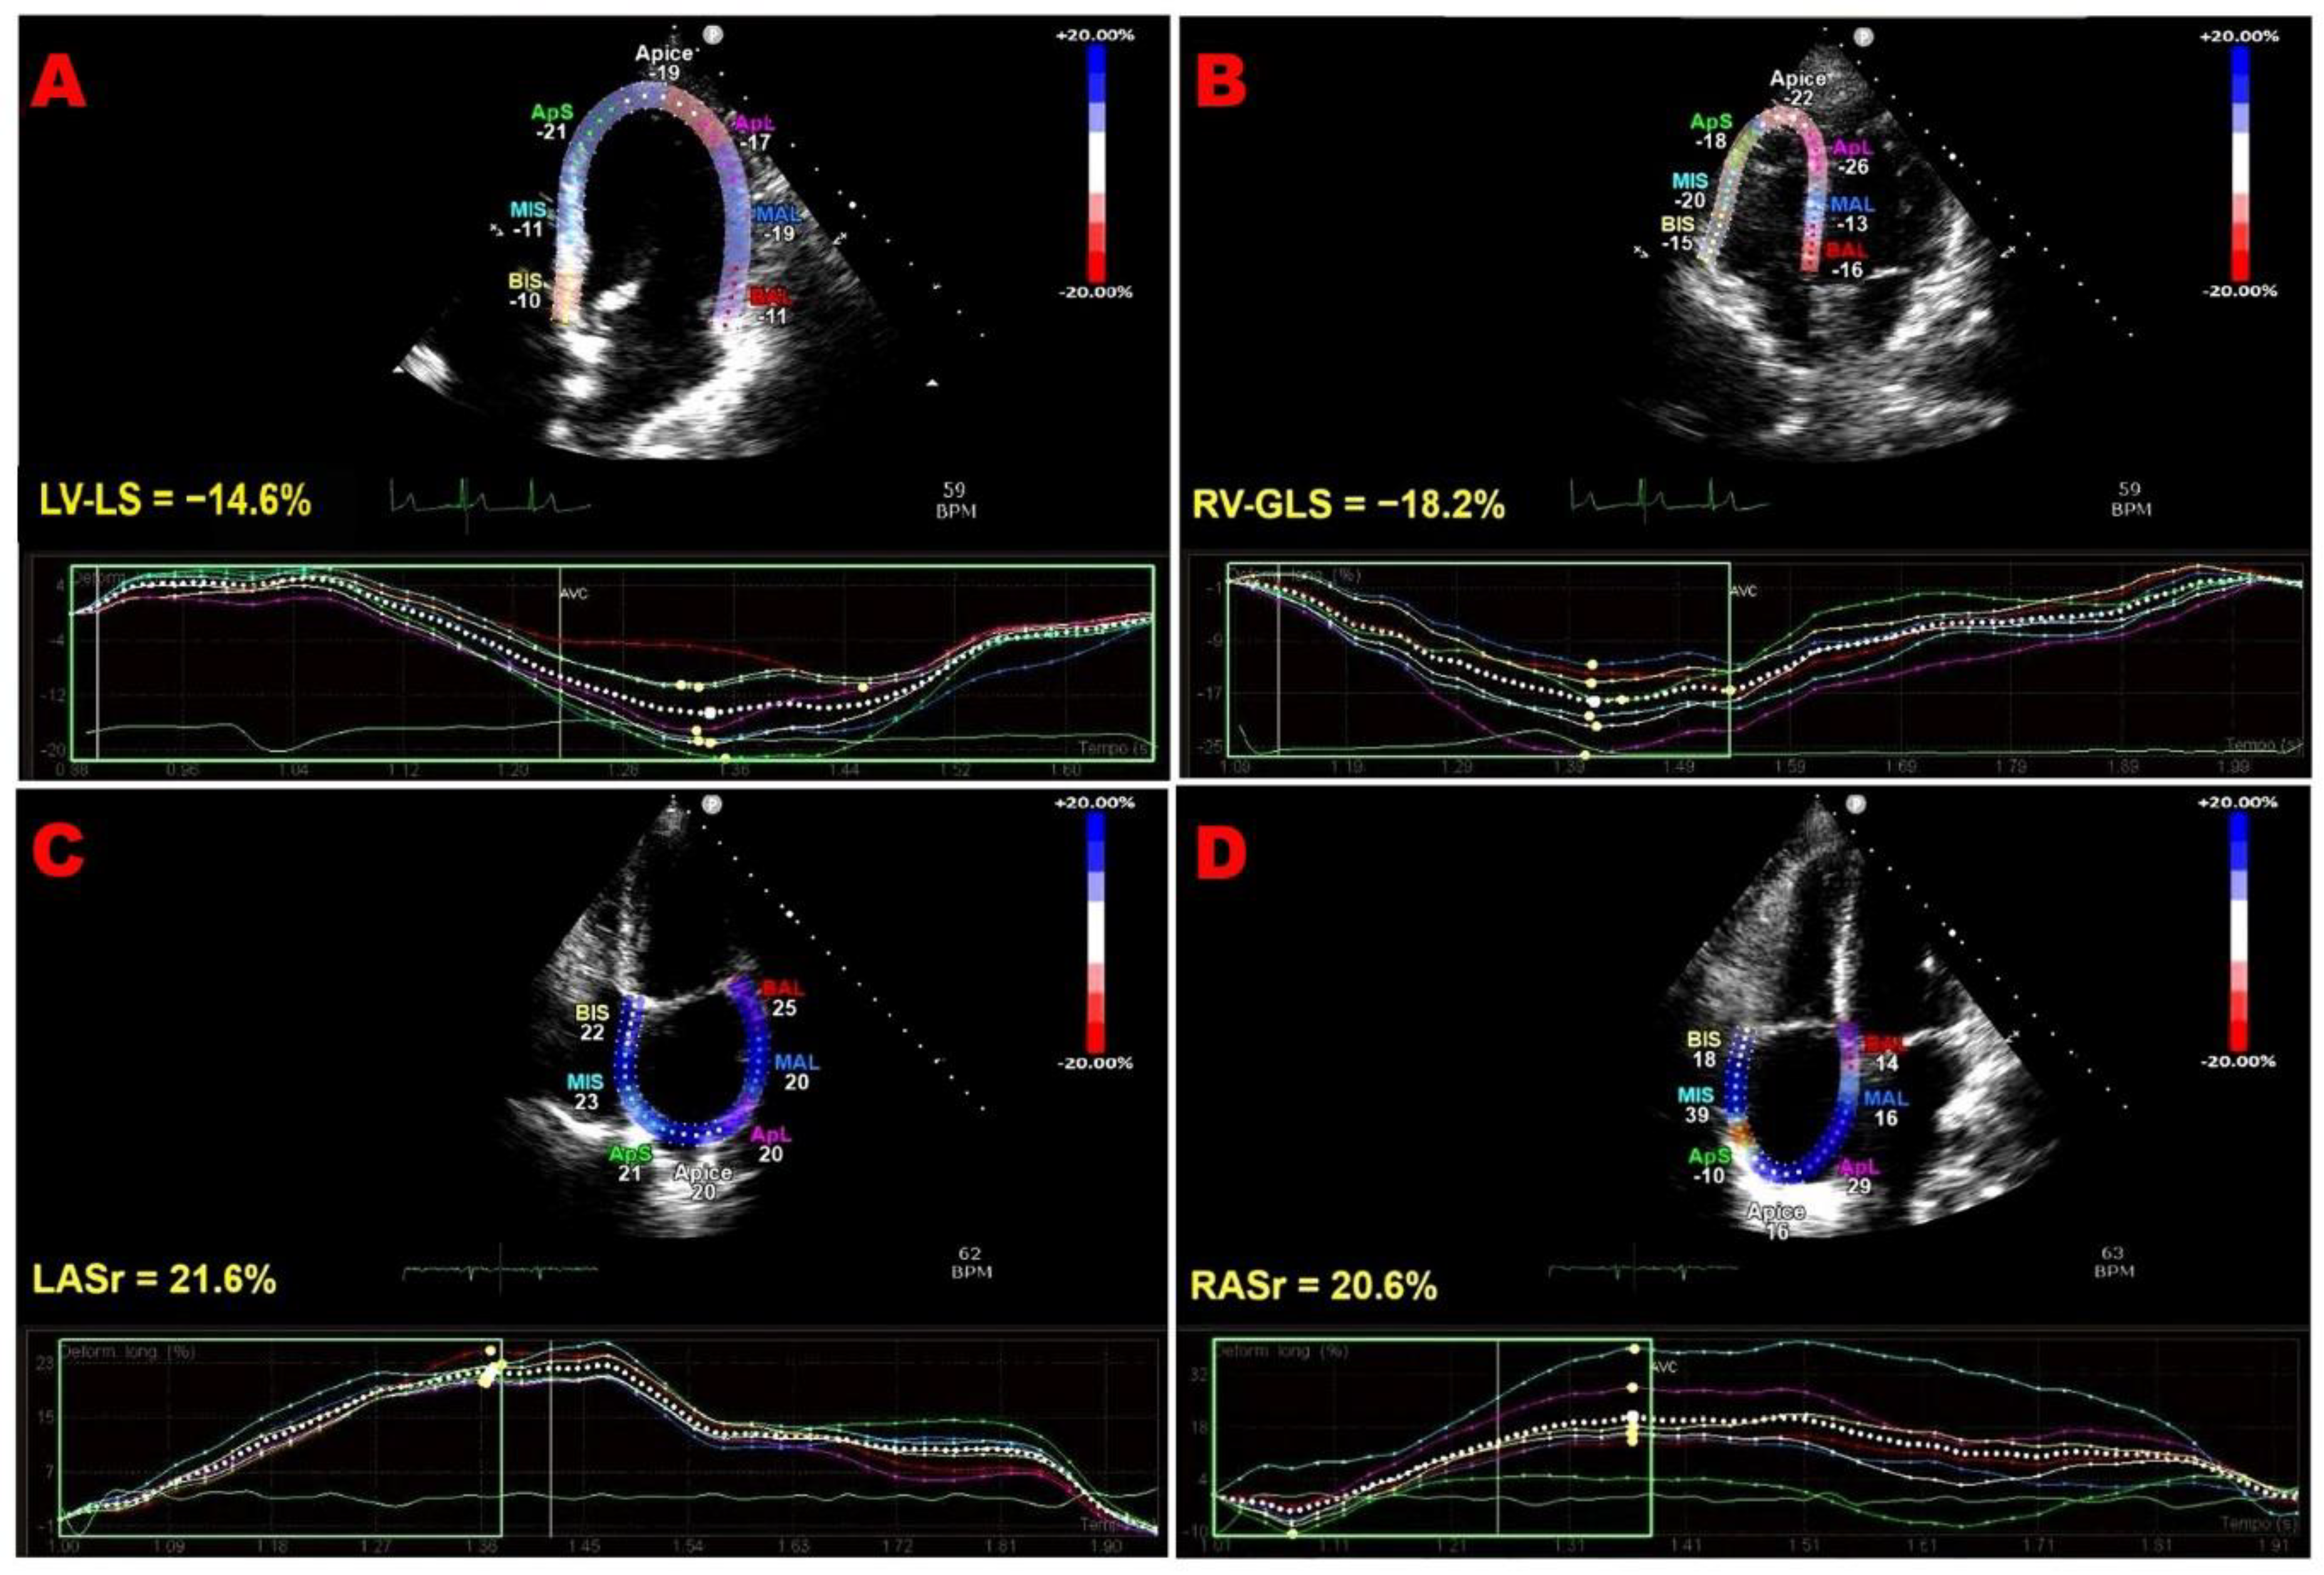

Figure 1 shows representative examples of biventricular and biatrial dysfunction identified by speckle-tracking echocardiography in an ICI-treated patient enrolled in the present study.

Figure 1. Representative examples of biventricular and biatrial myocardial strain parameters assessed by speckle-tracking echocardiography from the apical four-chamber (4C) view in an ICI-treated patient enrolled in the present study who developed ICI-related cardiac dysfunction. (A) LV-LS, left ventricular longitudinal strain. (B) RV-GLS, right ventricular global longitudinal strain. (C) LASr, left atrial reservoir strain. (D) RASr, right atrial reservoir strain. For each cardiac chamber, color-coded segmental strain maps are provided together with the corresponding strain curves. ICI, immune checkpoint inhibitors.